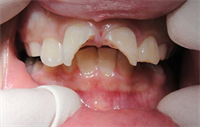

Dentaltown Learning Online..."Crooked to Straight: A General Dentists Journey Using Multiple Technologies" by Dr. Paul Caselle.

Dentaltown Online CE now has online "Crooked to Straight: A General Dentists Journey Using Multiple Technologies" by Dr. Paul Caselle. This course can be found here.... In a general dentistry practice it is very common to see patients who have orthodontic relapse and want some esthetic...  Read More